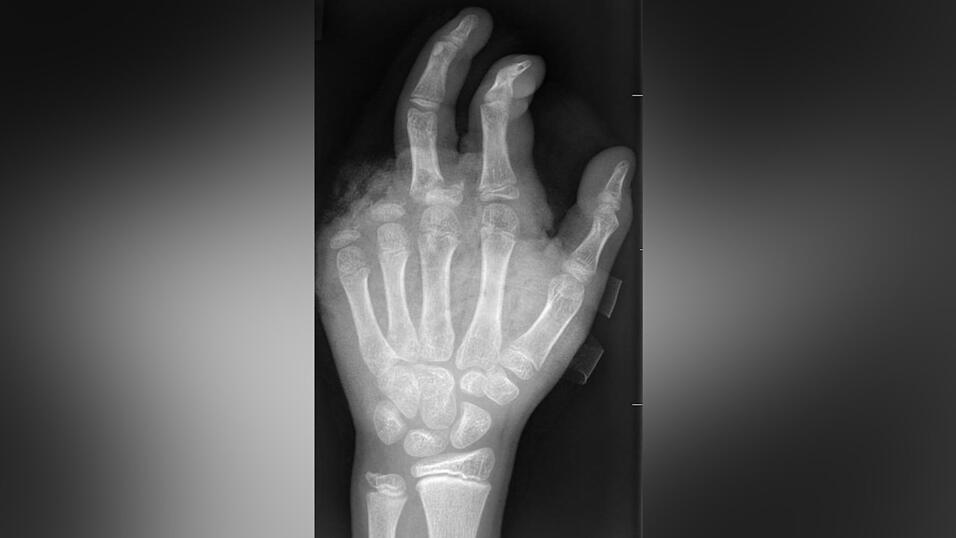

Abgetrennte Finger, durchtrennte Sehnen, Amputationen - die Handchirurgin Leila Harhaus-Wähner hat in der Silvesternacht schon vieles gesehen. Auch in diesem Jahr rechnet die Berliner Ärztin mit zahlreichen Böller-Verletzten. „Für Handchirurgen ist es klar, dass Silvester die arbeitsreichste Nacht sein kann.“ Bis 24 Uhr passiere erstmal nicht so viel, ab 1 Uhr, 2 Uhr nachts kämen immer mehr Verletzte in die Notaufnahme und dann „sehr viele in sehr kurzer Zeit.“

In der Handchirurgie müssten an Silvester im Unfallkrankenhaus rund 20 bis 40 Menschen mit Böllerverletzungen operiert werden, sagt die Ärztin. Dieses Jahr werde sie mir vier weiteren Handchirurgen im Einsatz sein. Die häufigsten Verletzungen entstünden durch explodierende Böller in der Hand.

„Der überwiegende Teil der Verletzungen trägt tatsächlich lebenslange Folgen mit sich, weil die Sprengkraft dazu führt, dass eben nicht nur einzelne Strukturen verletzt sind, sondern immer mehrere. Und das heilt praktisch nie ganz folgenlos ab.“ Zum Teil könnten Hände nicht mehr gerettet und müssten amputiert werden.